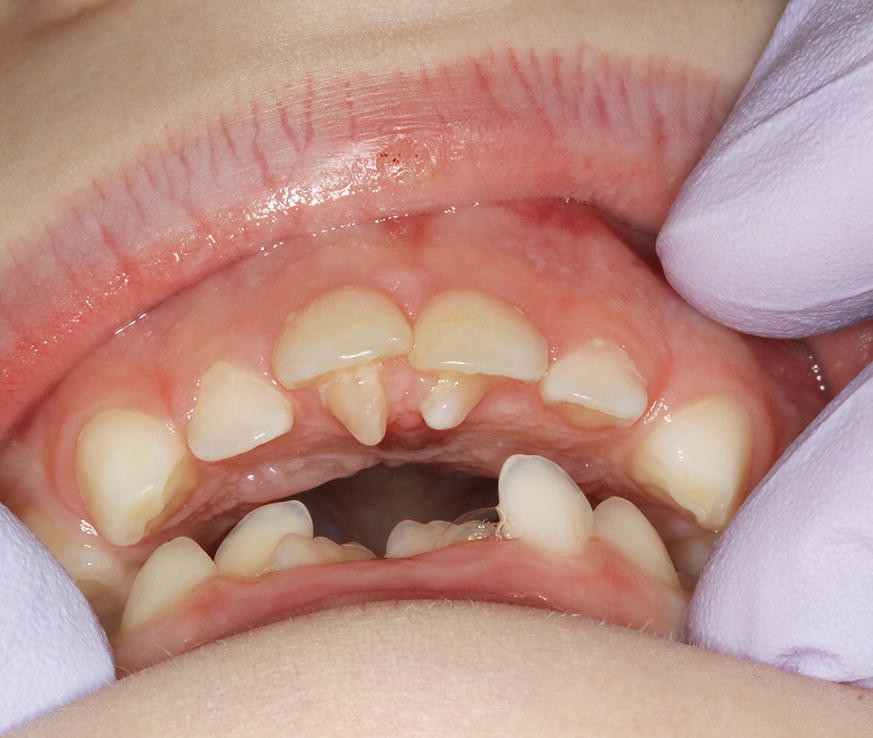

To explore these questions, Owaise Sharif and co-authors carried out a service evaluation of the joint dento-alveolar (JDA) clinic at the Croydon University Hospital. A prospective patient note analysis was carried out of 100 new patients attending between November 2014 and September 2015. Fifty-four percent of the patients were female, with the mean age 17 years. The most common anomalies referred were:

Impacted canines (49%)

Supernumeraries (16%)

Impacted second premolars (10%).

In addition to the service analysis described in part 1 of the BDJ series, in part 2 the authors provide an overview of common dental anomalies. Their definition, classification, aetiology and prevalence have been outlined along with their diagnosis and management. The aim of this is to increase awareness amongst practitioner's and help them formulate appropriate treatment plans. Part 1 of the series covers soft tissue anomalies, dentigerous cysts, transpositions and supernumerary teeth. Whereas part 2 focuses on impacted teeth, delayed and failed eruption, ankylosed incisors and infra-occluded deciduous molars.

Dental anomalies are often asymptomatic and may develop from an early age, the GDP therefore has a crucial role in early identification and management. In addition, dental anomalies often require onward referral to a specialist for management and so knowledge of potential management strategies will aid the GDP in counselling patients.

The average age of patients presenting to the clinic with impacted canines was 17 years, this is a late presentation age. Impacted canines are a common dental anomaly and although there are a number of reasons for late referral, this service evaluation has highlighted an area where knowledge improvement may be beneficial. The age of presentation for unerupted central incisors was also late. We hope that the information presented in this two part series is useful for the whole dental team.